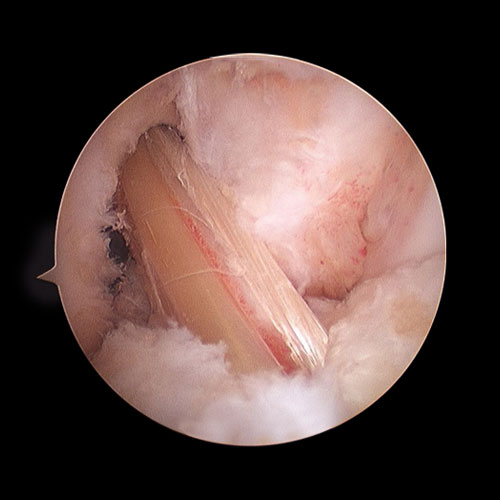

Nato a Roma nel 1953, laureato in Medicina e Chirurgia, specialista in Ortopedia, attualmente Dirige la Struttura Complessa di Ortopedia e Traumatologia presso l’Ospedale Cristo Re, Roma e presso la Casa di Cura Paideia. Si occupa di Ortopedia con particolare riferimento alla chirurgia artroscopia e protesica anche con l’uso del navigatore e di Traumatologia.

L’ortopedico: «L’artrosi del Pontefice è recente. Viene curata con antinfiammatori o cortisone»